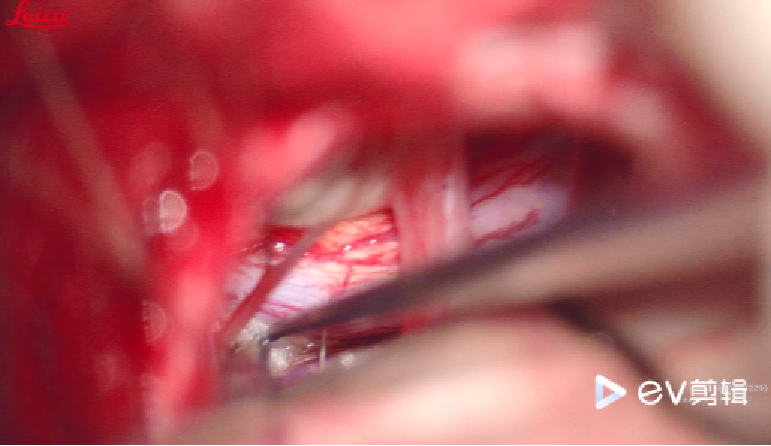

在舌咽迷走神经腹侧,见椎动脉及PICA主干压迫,予以teflon垫入

椎动脉压力传导大,予以椎动脉尾端垫入teflon架桥

在面神经下腹侧,在PICA分支和REZ区垫入teflon